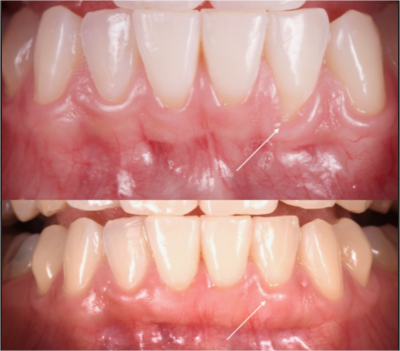

Les greffes de gencive

La gencive joue un rôle essentiel dans la préservation de la dent et du parodonte. Elle protège à la fois le tissu osseux et les dents qui sont les seules organes vivants contenus à la fois dans un milieu stérile (l’os) et un milieu septique (la bouche). La récession gingivale communément appel...